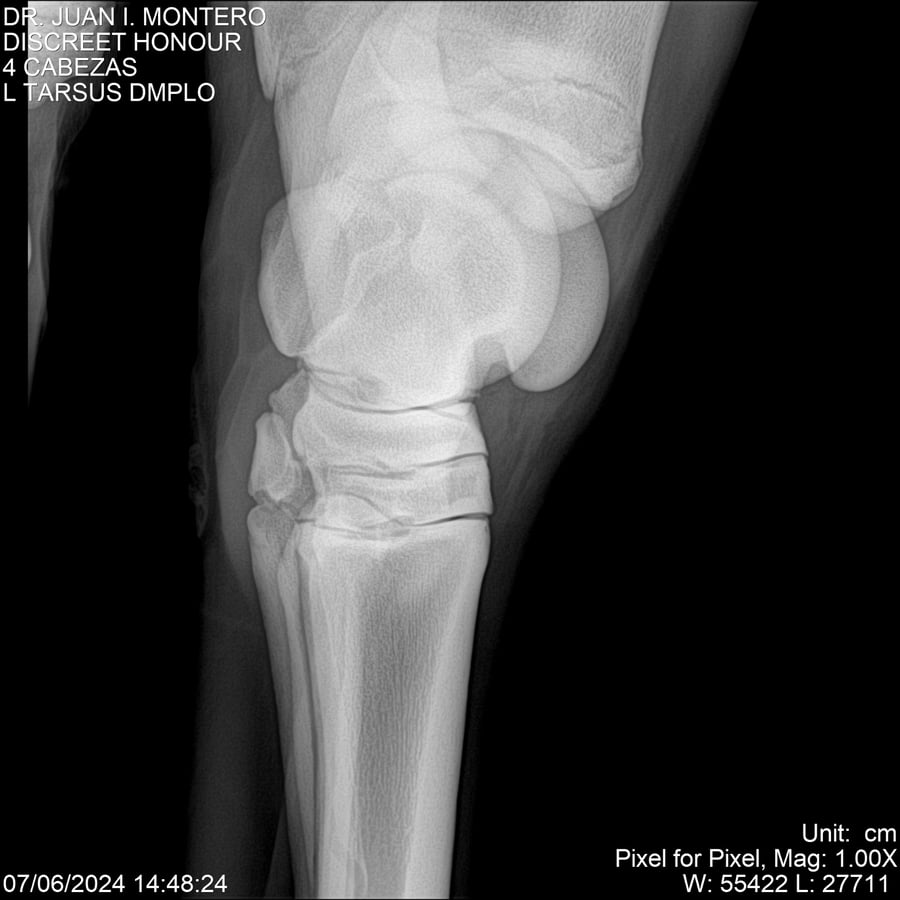

LOTE 6, DISCREET HONOUR 🔥 🔥 🔥 Lote Anterior Volver al remate Lote Siguiente Ficha Contacto Montevideo - Ficha del Lote Identificador: #281093 Categoría: Yeguarizos Montevideo - 82 Visualizaciones ClicData Contacto Empresa: Abelenda N. R., Walter Hugo Nombre*: Teléfono* : E-mail* : Mensaje Enviar Registrese gratis Este contenido Exclusivo está disponible sólo para usuarios registrados Ingresar